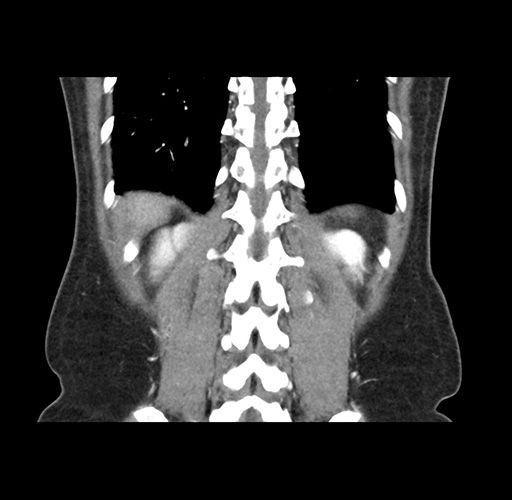

Imaging Analysis

Look through the patient's CT scan to identify any areas of concern for the necessary procedure.

Based on your CT findings, which issue(s) would give reason for "planned slowing down moment(s)" in this case?